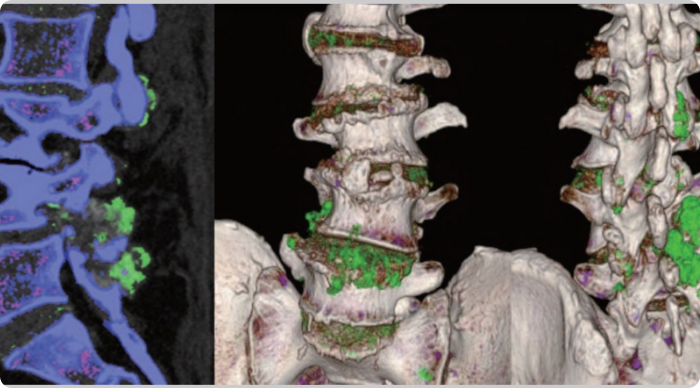

DECT scans of lower spine showing tophaceous deposits

Sagittal DECT and 3-dimensional DECT reconstruction show extensive tophaceous deposits (in green) in L1/2, L2/3, L3/4, and L4/5 lumbar discs, and also L2-L3 and L4-L5 facet joints.2

Adapted from Lu H, et al. Medicine (Baltimore). 2017;96:e7670.

KRYSTEXXA has not been studied to reverse damage to the spine or any of the body's organ.

DECT, dual-energy computed tomography.

DECT scans of lumbar spine showing tophaceous deposits

Sagittal mixed 120-kVp equivalent images of lumbar spine obtained with dual-energy CT demonstrate an intermediate-attenuation mass in the L5-S1 facet joint with bony erosions and narrowing of the neural foramen (arrow, left). Dual-energy material labeling color map overlay shows monosodium urate (green) and bone (blue and pink). Note the monosodium urate crystals crowding the left neural foramen (arrow, right).3

Adapted from Gibney B, et al. Radiology. 2020;296:276.

CT, computed tomography.